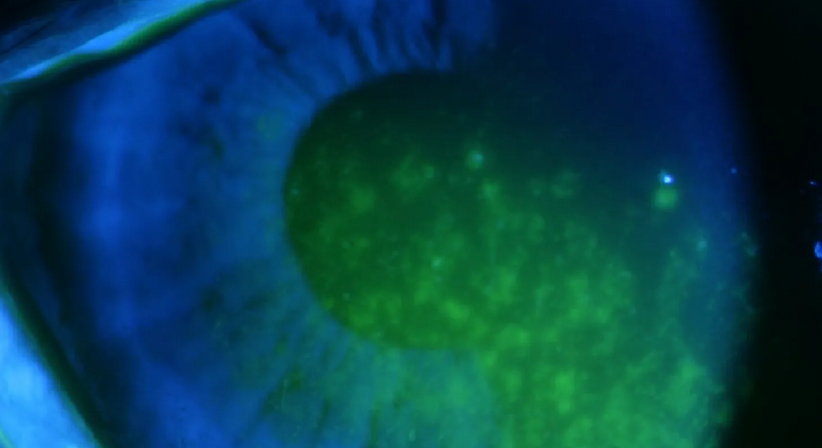

Mit dem Begriff „Trockenes Auge“ wird eine Benetzungsstörung der Augenoberfläche bezeichnet, die durch eine Verminderung der Tränenmenge (quantitative Tränenfilmstörung) oder durch eine veränderte Zusammensetzung der Tränenflüssigkeit (qualitative Tränenfilmstörung) hervorgerufen wird.